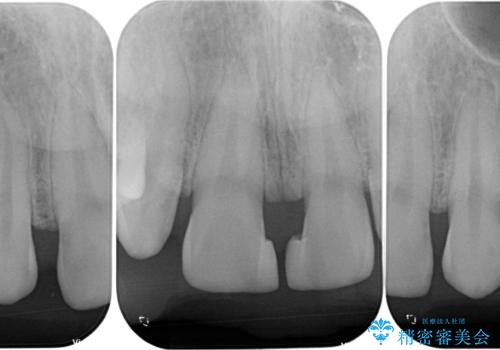

欠損して隙間のある前歯 オールセラミッククラウンで自然な口元に

- 歯の欠損による前歯のすきっ歯を気にして来院された患者様です。

矯正治療かオールセラミックか、治療の選択がありましたが、熟考の末オールセラミッククラウンにて補綴することとしました。

ひとつひとつの歯の幅は非常に大きくなりましたが、手っ取り早く隙間が改善されたとのことで、大変満足していらっしゃいました。